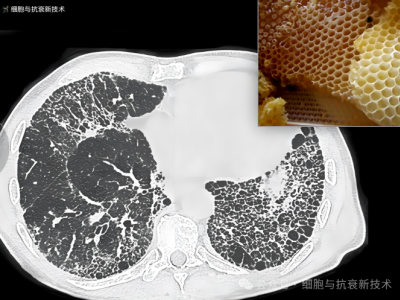

外泌體霧化可治療肺部結(jié)節(jié)及肺纖維化

2019年新冠疫情后,大家對肺部損傷比較關(guān)注,加之生活工作壓力以及檢測技術(shù)的進(jìn)步,使結(jié)節(jié)成為體檢報(bào)告上出現(xiàn)的高頻詞匯,其中包括肺部結(jié)節(jié),結(jié)節(jié)的出現(xiàn)給部分人群增添了焦慮。外泌體作為先進(jìn)治療藥品,是當(dāng)前生